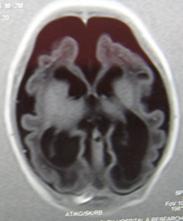

Figure 4: Holoprosencephaly

brain-malformations

What is holoprosencephaly?

Holoprosencephaly (pronounced as holo-pro-zen-ceph-a-lee) is a condition in which the brain fails to divide into two lobes and only a single lobe is present. This condition is common in patients with genetic syndromes. Most patients have severe delayed development, spasticity, and seizures.